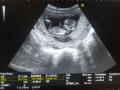

Desire con 22 semanas

Desire, con 22 semanas